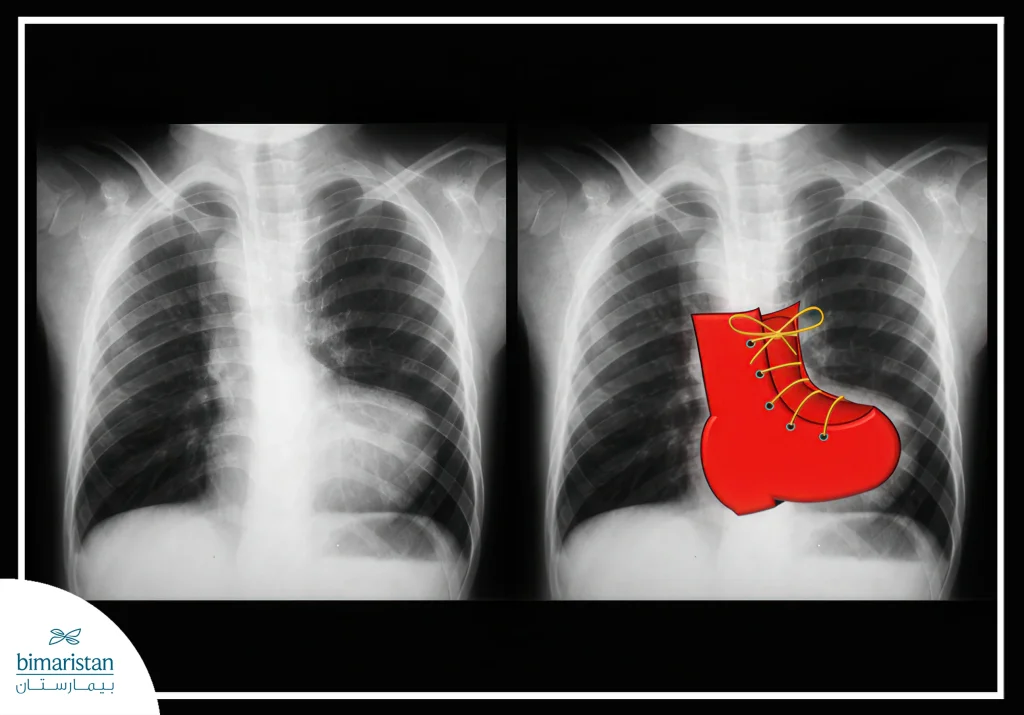

- Chest X-ray: Shows the shape of the heart and lungs, sometimes showing a shoe-shaped heart due to an enlarged right ventricle.